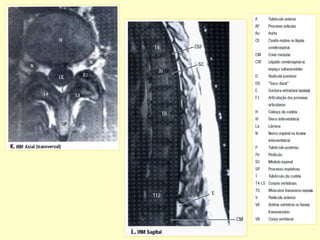

PADRÃO ‘ OURO’ PARA AVALIAR A

COLUNA POR MÉTODO DE IMAGEM

É A RESSONÂNCIA MAGNÉTICA.

Conteúdos intra-raquianos